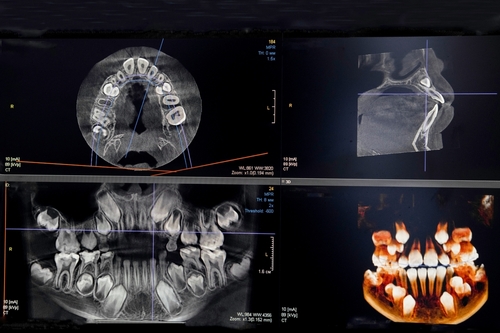

Precise Implant Placement Using Advanced Imaging

Technology That Supports Predictable Implant Placement